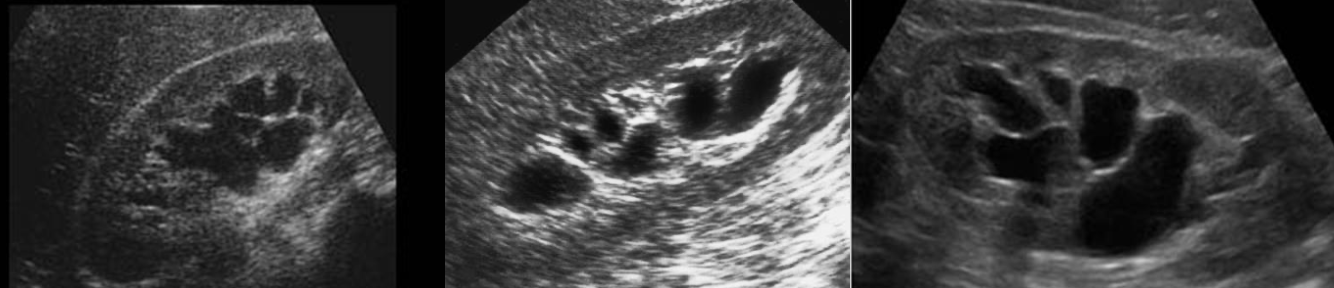

Hydronephrosis → dilation of renal collecting system from mechanical obstruction or functional dysfunction (calculi, mass, trauma, pregnancy)

clinical hx: prone to stones (stasis, pregnancy)

s/sx: if stone → renal colic, N&V, hematuria, frequency/urgency

2D US: grade 1 (mild) → pelviectasis, cortex preserved, grade 2 (mild to moderate) → expands into major calyces, cortex preserved, grade 3 (moderate) → expand all calyces, entire pelvis dilated, cortex preserved, grade 4 (severe) → cortical thinning, AKI to CKD, creatinine >1.2

color doppler: avascular

DDX: parapelvic cysts